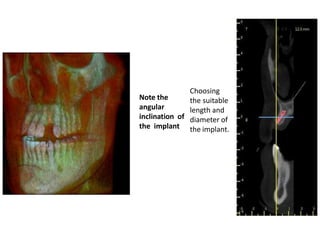

Note the

angular

inclination of

the implant

Choosing

the suitable

length and

diameter of

the implant.